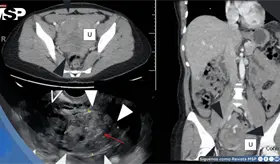

Las prótesis antiguas de metal con metal pueden liberar partículas microscópicas que generan inflamación severa, masas que imitan tumores malignos y, además, crean un ambiente propenso a infecciones profundas difíciles de tratar.